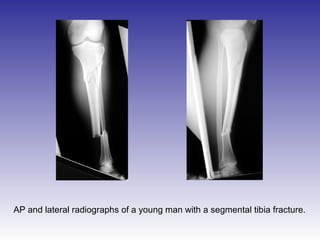

AP and lateral radiographs of a young man with a segmental tibia fracture.

AP and lateralradiographs of a young man with a segmental tibia fracture.